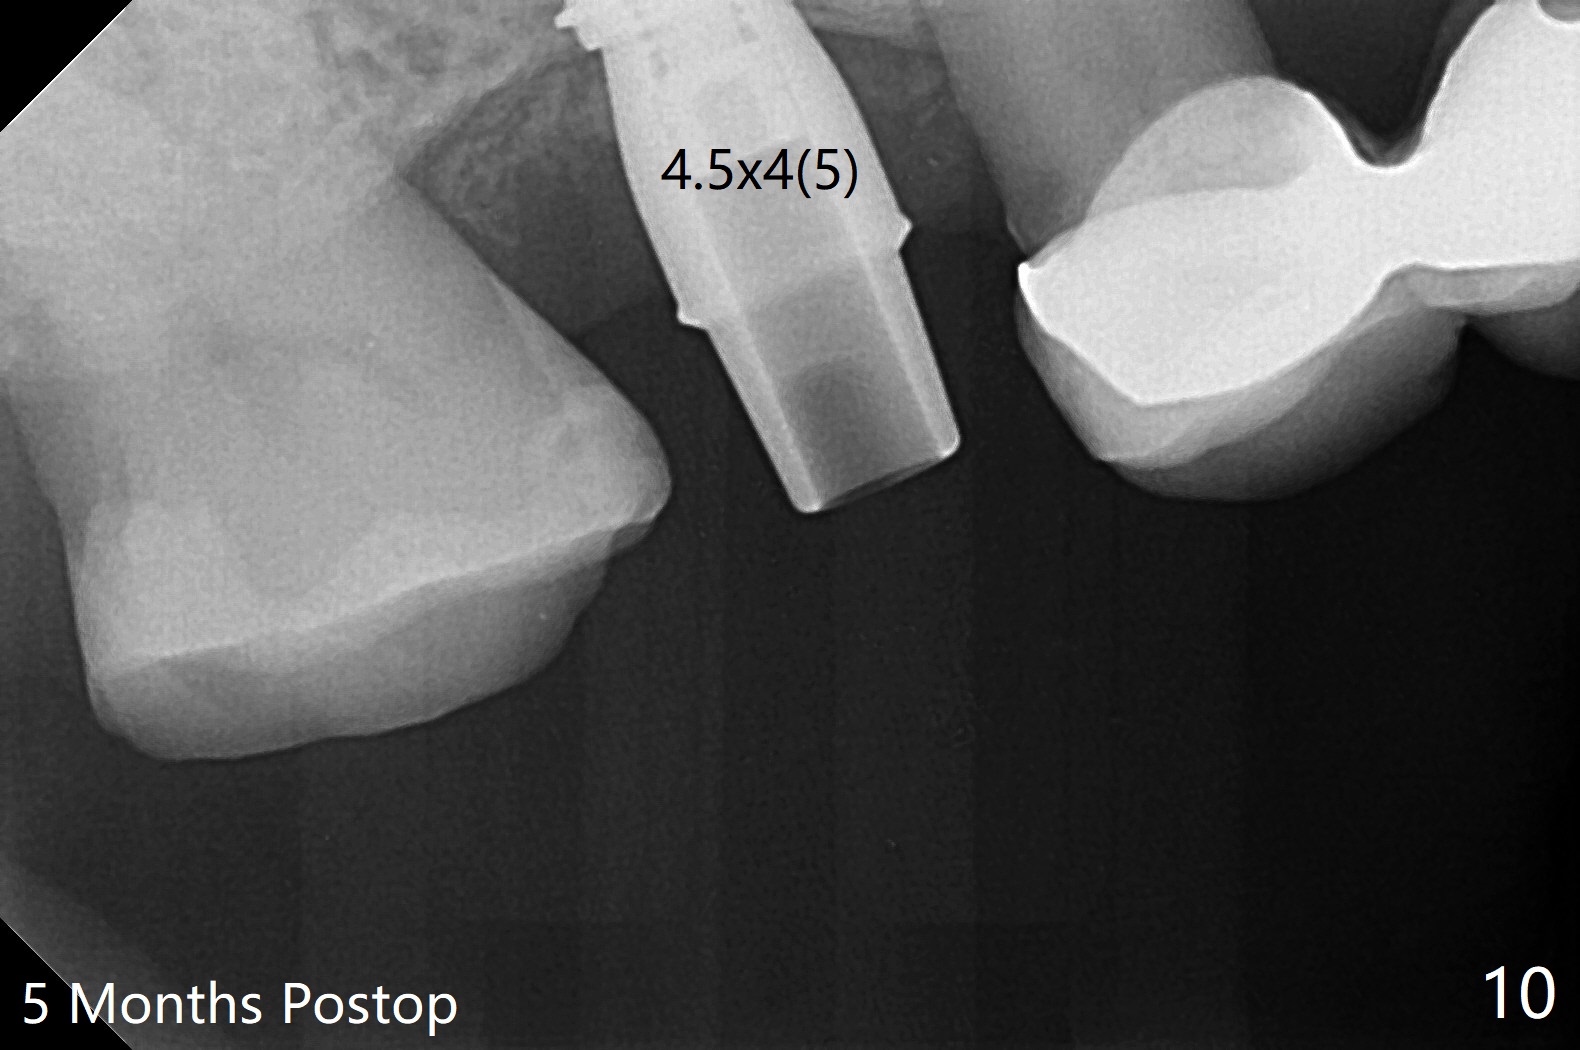

提取上清液后,红管再次离心,同样速度,5分钟,便形成PRF(胶状,上面黄色部分,图七),由于试管在离心机放置角度缘故,PRF与下面红血球部分(深色)交界处是一个斜面,制作PRF膜前,必须在交界处下面剪(图八白斜线),因为在交界处有效成分浓度最高,请看录像(虽然剪的太高些)。制作完毕的PRF膜可以覆盖图四骨块表面,但是用于图一之后,塞入上颌窦(录像),目的促进上颌窦膜修复,万一提升时出现隐形破裂。术后五个月放置5.5x4(4)毫米基台,未完全就位:基台与植体之间有间隙(图九:>),可能牙槽嵴阻挡(*),直径小的基台容易就位(图十),植体根尖空间(上下)也缩小(图十一)。